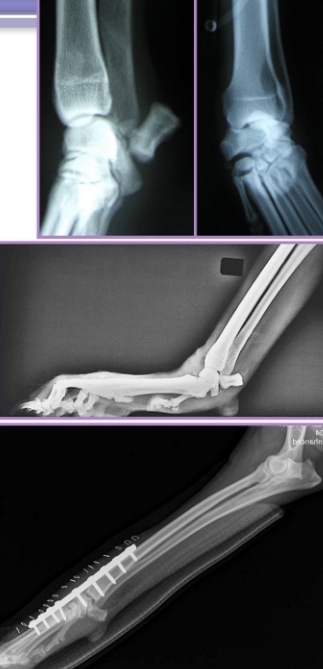

Carpal Hyperextension or Luxation

Et: Palmar fibrocartilage and ligaments torn of loss of support

fall or hyperextension injury

Cs: Non-weightbearing lameness, Stand with carpus hyperextended, Palmigrade stance

Dt: Radiographs

Tx: arthrodesis

Splinting does not work

Tarsal Injuries

Et: Usually shearing injuries

Collateral instability, Open fractures, Sheared bone, Soft tissue injury

often medial collateral damaged → excessive valgus

Tx: Reconstruction, Arthrodesis

Arthrodesis

Use: Salvage procedure, for carpals/tarsals

Tarsal injuries, Carpal Hyperextension, Carpal Luxation, Shoulder Luxation

How: Permanent fusion of joints with plates, screws, pins or ESF

Remove cartilage and maintain limb at normal standing angle

Px: Eliminates flexion/extension of joint and results in mechanical lameness